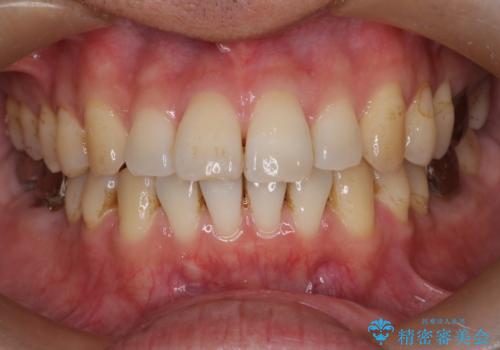

- 前歯の出ているのが気になる、下唇を噛んで痛いとのことで来院された患者様です。マウスピース矯正をご希望でした。

奥歯の噛み合わせはしっかりしていましたので、奥歯の動きは最小限にし、前歯の並びに集中した治療計画+インビザラインのシミュレーションを作成しました。

奥歯の噛み合わせは整っていたため、前歯の並びを美しく修正することに専念できました。マウスピース矯正による治療で短期間で改善しました。